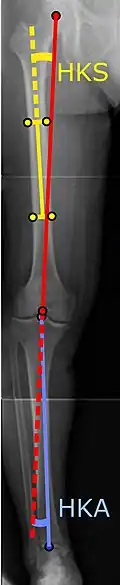

|

Angles commonly measured before knee replacement surgery: |

To indicate knee replacement in case of osteoarthritis, its radiographic classification and severity of symptoms both should be substantial. Such radiography should consist of weightbearing X-rays of both knees: AP, lateral, and 30 degrees of flexion. AP and lateral views may not show joint space narrowing, but the 30-degree flexion view is most sensitive for narrowing. Full-length projections also are used in order to adjust the prosthesis to provide a neutral angle for the distal lower extremity. Two angles used for this purpose are:

- Hip-knee-shaft angle (HKS),[10] an angle formed between a line through the longitudinal axis of the femoral shaft and its mechanical axis, which is a line from the center of the femoral head to the intercondylar notch of the distal femur.[12]

- Hip-knee-ankle angle (HKA),[11] which is an angle between the femoral mechanical axis and the center of the ankle joint.[12] It is normally between 1.0° and 1.5° of varus in adults.[13]